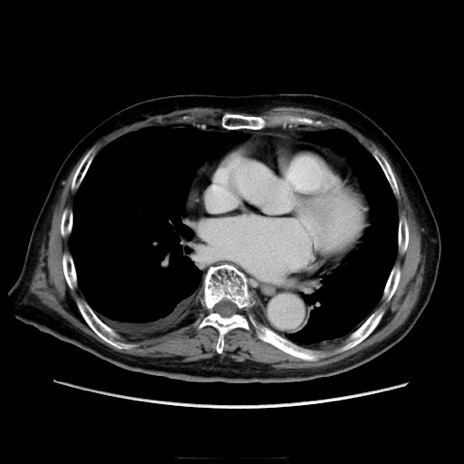

冠状断像

【症例】70歳代男性

【現病歴】肝硬変・肝細胞癌にてかかりつけの方。約9時間前に食後より腹痛出現。症状が徐々に増悪し、嘔吐出現したため来院。

【既往歴】肝硬変、肝細胞癌(RFA、TACE後)